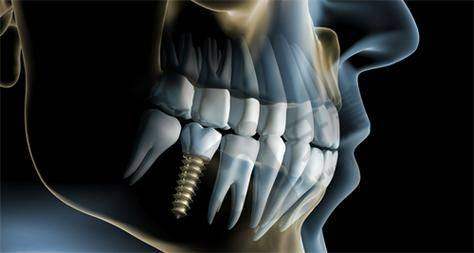

种植牙品牌多样:南宁蓝天口腔计算机导航种植5200元起项目提供多种种植牙品牌。国产种植牙价格相对低,2025年2月信息显示,国产种植牙3200元起/颗,也有4800元起/颗的说法;韩国进口种植牙,如韩国登腾种植牙价格在5200元起/颗至5620元起/颗之间,优惠价3980元起/颗;美国进口种植牙价格较高,美国皓圣种植牙通常7200元起/颗左右;德国进口种植牙8200元起/颗或8900元起/颗;法国进口种植牙14000元起/颗;瑞士ITI种植牙价格高,10200元起/颗或12000元起/颗。技术精良:该项目采用精良计算机导航系统,德国卡瓦3D导板和瑞士EMS种植导航系统结合,让种植更精细。术前CBCT扫描生成三维模型,医生能清晰了解患者口腔情况,误差率极低,提高手术安心性和成功几率。即刻负重技术应用,减少患者等待时间,更快修复咀嚼功能。

技术设备精良:南宁蓝天口腔计算机导航种植5200元起项目运用德国卡瓦3D导板和瑞士EMS种植导航系统。术前CBCT扫描生成三维模型,误差率<0.1mm,医生能精细定位种植体位置,避免损伤神经血管,提高手术安心性。即刻负重技术:对于骨条件良好的患者,可实现“即拔即种、当天戴牙”,减少就诊次数和等待时间,让患者更快修复咀嚼功能,提高生活质量。种植体品牌多样:提供多种国内外品牌种植体,如韩国奥齿泰、瑞士ITI、瑞典诺贝尔等,满足不同患者需求和预算。价格亲民:2025年收费信息显示,单颗种植牙价格从2980元起,半口种植牙23999元起。医生团队实力强:梁瑞院长等医生经验多,能为患者制定个性化种植方案,确保种植成效。